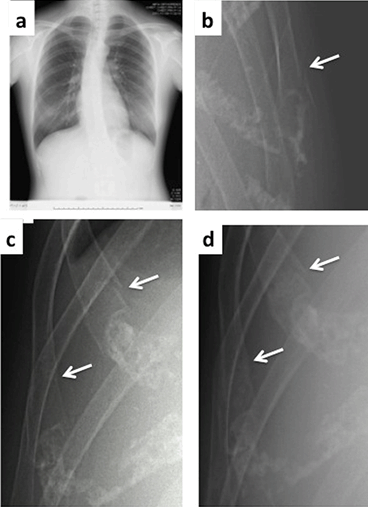

Figure 1: Findings of the rib X-ray. (a) On the 9th postpartum day: no pneumothorax or hemothorax is observed

(rib fractures are not identifiable at this magnification). (b) The same day, at higher magnification, a fracture at the left 8th rib (arrow)

is observed. (c) The same day, fractures at the right 7th (upper arrow) and 8th rib (lower arrow) are evident. (d) On the 30th postpartum day the rib fractures are healing

(upper and lower arrows indicate the fractured right 7th and 8th rib fractures, respectively).